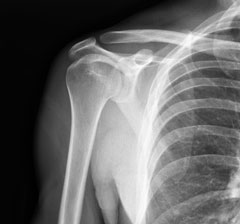

Risque de refracture et de décès selon la densitométrie osseuse chez des femmes et des hommes âgés ayant présenté une fracture par fragilité osseuse : résultats de l’étude DUBBO

Dans l’ostéoporose post-ménopausique, la moitié des fractures par fragilité osseuse surviennent chez des individus ayant une DMO non ostéoporotique (T score > -2,5). Cette proportion est encore plus importante au cours de l’ostéoporose masculine (environ 70%).

Nous ne disposons que de peu d’éléments concernant la refracture et la mortalité après une 1ère fracture de fragilité en fonction des résultats de la DMO (normale, ostéopénie ou ostéoporose). L’objectif de ce travail était donc de déterminer les risques de refracture et de décès à la suite de d’une 1ère fracture selon les niveaux de la DMO.